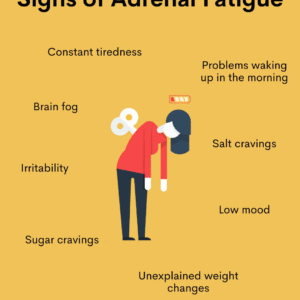

Adrenal Exhaustion (chronic fatigue)